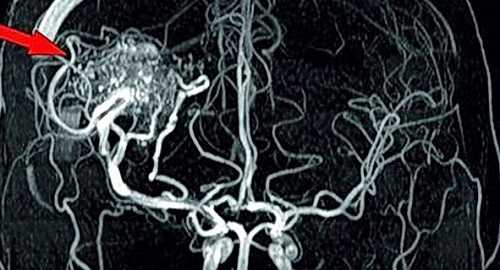

Артерио-венозная мальформация (стрелка)

Сканирование с болюсным усилением проводят в два этапа: после серии нативных снимков делают инъекцию раствора гадолиния. Препарат заполняет кровеносное русло и межклеточное пространство, визуализируя изменения каналов и окружающих тканей.

Контрастная МРТ артерий головного мозга показывает новообразования сосудов и церебральных структур на начальных стадиях формирования. На снимках определяются опухоли диаметром от 3 мм.